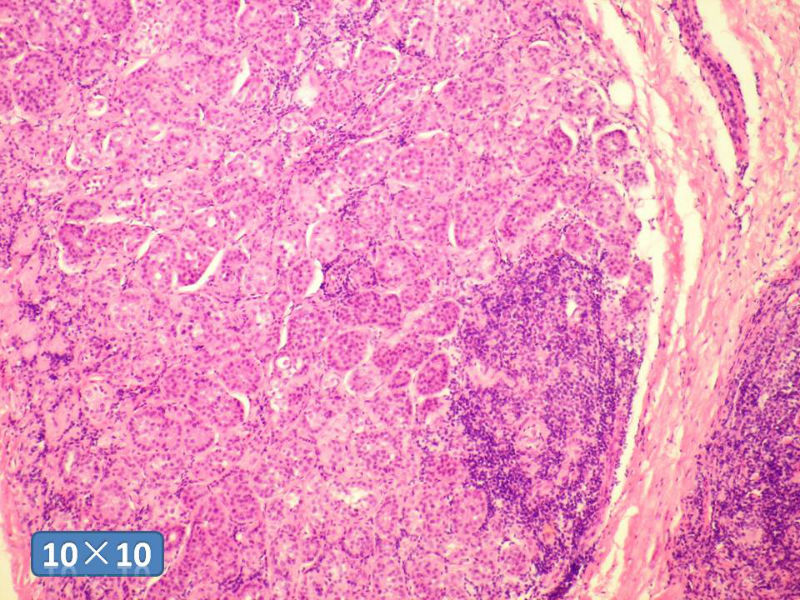

女性,50岁,乳腺肿物,冰冻切片(图1-25)

HE

IDC